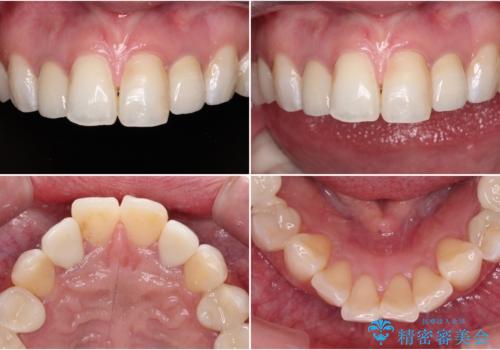

金属の見えてしまったクラウン セラミッククラウンで自然に

- クラウンから金属の土台が見えてきてしまったとのことで、作り替えを希望して来院された患者様です。

前歯や金属が露出している歯、痛みを感じる歯を中心に、オールセラミッククラウンにて補綴治療することとしました。

以前はセラミッククラウンのフレームとして金属が使用されており、歯肉の経年変化やセラミックのすり減りなどにより、金属が見えるようになってくることがあります。

現在は金属の代わりに強化セラミックを使用したオールセラミッククラウンが主流です。金属色が気になる方はご相談ください。